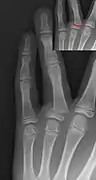

• Type III – A fracture through growth plate and epiphysis, sparing the metaphysis:[9] 8% incidence